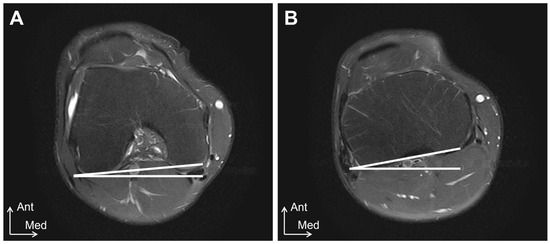

All MRI examinations were performed using a 1.5T system (Oval; HITACHI, Chiba, Japan), with the extremity coils being used as receiver coils. The knee joint was selected as the imaging site for this study. Measurements were performed in the prone position with the knee joint in full extension, and the center of the patella was positioned at the center of the receiver coil. The MRI measurements were performed by a single radiologist. The tibial external-rotation angle was evaluated using axial images, as described by Vassalou et al. [13] (Figure 2). The femoral rotation angle was defined as the angle between the horizontal line and the line of the subchondral bone of the posterior femoral condyle at the most prominent point [13]. The tibial rotation angle was defined as the angle between the horizontal line and the line of the posterior cortical margin of the tibial condyles using one slice above the head of the fibula [13]. The tibial external-rotation angle was calculated by subtracting the femoral rotation angle from the tibial rotation angle; it was assigned a positive value for the external rotation and a negative value for the internal rotation.

Figure 2.

MRI tibial external-rotation angle measurement method. (A) femoral rotation angle. The femoral rotation angle was defined as the angle between the horizontal line and the line of the subchondral bone of the posterior femoral condyle at the most prominent point. (B) tibial rotation angle. The tibial rotation angle was defined as the angle between the horizontal line and the line of the posterior cortical margin of the tibial condyles using one slice above the head of the fibula. Ant, anterior; Med, medial.